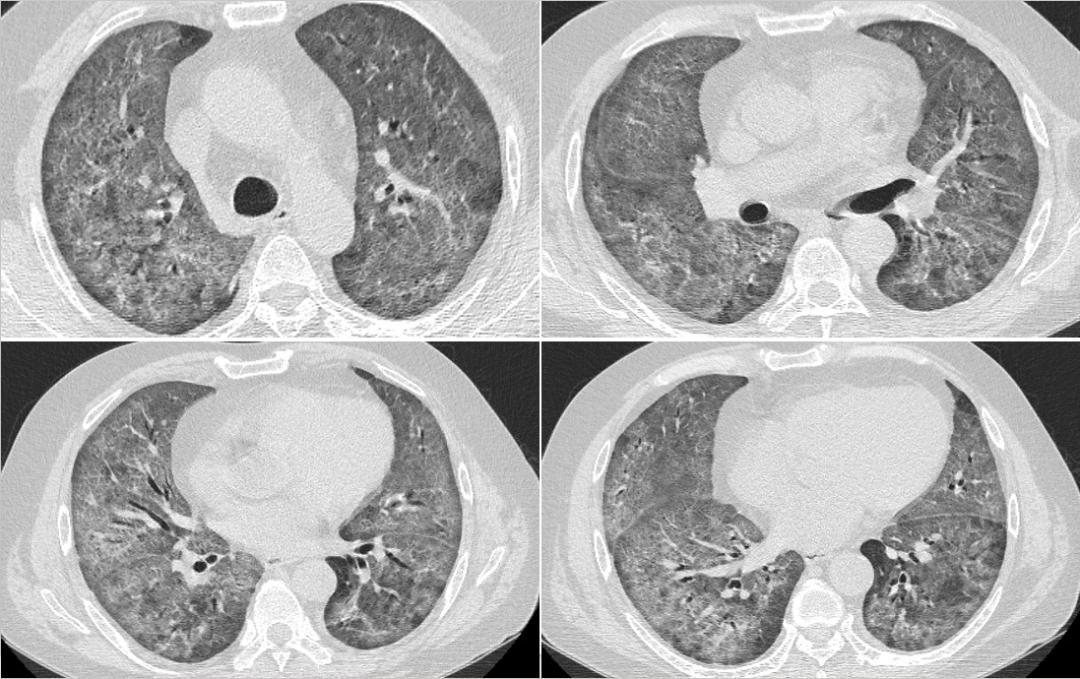

2022-7-13胸部CT

临床病例(三):甘某某,男,50岁,2022年7月12日因「发热,、咳嗽、咳痰、气喘10余天,加重2天」入院。痰色白不易咳出,体温最高38.5℃。外院予「莫西沙星+头孢他啶」抗感染,「甲强龙40mg」抗炎,仍反复发热,2天前咳嗽、咳痰、气喘加重。

既往史及个人史:2022年2月于广西省人民医院行「肾移植术」,后规律服用「吗替麦考酚酯胶囊、他克莫司」抗排斥。

查体:T 37.3℃,P 118次/分,R 25次/分,BP 118/89mmhg。双肺呼吸音粗,未闻及干湿性啰音和胸膜摩擦音。心腹查体未见明显异常。

血气分析:PCO2:26.9mmHg↓、PO2:56.2mmHg↓、实际碳酸氢根17.2mmol/L↓、标准碳酸氢根19.8mmol/L↓、总CO2:40.5mmol/L↑、实际剩余碱-5.4mmol/L↓、标准剩余碱-6.4mmol/L↓、氧饱和度88.9%↓、氧合血红蛋白86.6%↓、还原血红蛋白10.8%↑、P50:26.55↓。

血常规:白细胞 8.22X10^9、粒细胞百分比 85.1%↑、粒细胞计数 7.65X10^9↑、淋巴细胞百分比 7.4%↓、淋巴细胞计数 0.45X10^9↓、嗜酸性细胞百分比 0%。

CRP:106mg/L↑

诊治经过如下:

患者既往有肾移植病史,使用激素及免疫*制剂抑**,此次肺炎病情进展迅速,胸部CT影像学符合PJP或巨细胞病毒改变,需立即给予PJP及更昔洛韦诊断性治疗,并积极完善纤维支气管镜肺泡灌洗明确病原菌。

2022年7月14日的BALF-mNGS结果,检出耶氏肺孢子菌。

患者的呼吸道病原体谱抗体,EB病毒、巨细胞病毒DNA,肺炎支原体,T-SPOT,术前四项均未见异常。

2022年7月17日:患者气喘较前明显好转,改口服SMZ;7月18日:复查胸部CT。患者仍有活动性气喘,暂续前治疗;7月20日:气喘明显加重,急查血气;7月22日:炎症指标上升,转ICU行气管插管+呼吸机辅助呼吸,CRRT。

2022年7月18日,患者胸部CT见双肺间质性炎症范围较前扩大,考虑PJP感染导致的间质性炎症持续渗出。

患者属重症PJP,给予静脉使用SMZ注射液病情一度好转,但因经济原因,改为口服SMZ治疗,后病情进展迅速。